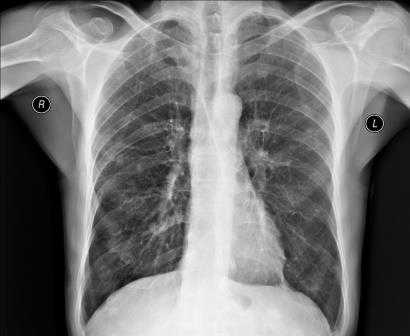

Рентгенография грудной клетки

Рентгенография грудной клетки – это метод диагностики, позволяющий получить изображение органов грудной полости с помощью облучения рентгеновыми лучами. Различные ткани организма в зависимости от своей плотности по-разному пропускают рентгеновы лучи, а значит, по-разному отображаются на снимке (рентгенограмме).

Рентген грудной клетки дает возможность изучить костные структуры (ребра, грудину, позвоночник), легкие, плевру, бронхи и трахею, сердце и средостение, а также оценить состояние мягких тканей этой области.

Что показывает рентген грудной клетки у взрослого

Рентгенография как метод диагностики широко известна и является базовым обследованием ряда заболеваний. В этой статье вы найдете информацию о том, что показывает рентген грудной клетки у взрослого. А также ответы на частые вопросы об этом обследовании. Итак, рентген органов грудной клетки показывает патологии легких, бронхов, сердца, перелом ребер, повреждения позвоночника в грудном отделе. Врач назначает обследование грудной клетки при подозрении на следующие заболевания: туберкулез, пневмония, бронхит, онкология дыхательных путей, порок сердца, заболевание сердечной мышцы. А также диагностика эффективна при оценке травматических повреждений грудной клетки.

Что можно увидеть на рентгене ОГК?

В обзор снимка попадают органы дыхания (легкие, трахеи, бронхи), диафрагма, мышцы, лимфоузлы, сердце и кости (ребра, позвоночный столб, лопатки, ключица, грудина). Обследование делается по назначению врача и поэтому рентгенолог усиливает внимание на ту область, в которой необходимо подтверждение или опровержение предполагаемого диагноза.